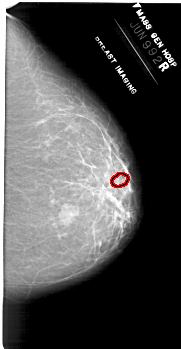

A_1953_1.RIGHT_CC

RIGHT_CC LINES 6616 PIXELS_PER_LINE 3436 BITS_PER_PIXEL 12 RESOLUTION 43.5 OVERLAY

FILE: A_1953_1.RIGHT_CC.OVERLAY

TOTAL_ABNORMALITIES 1

ABNORMALITY 1

LESION_TYPE CALCIFICATION TYPE PLEOMORPHIC DISTRIBUTION CLUSTERED

ASSESSMENT 4

SUBTLETY 1

PATHOLOGY BENIGN

TOTAL_OUTLINES 1

BOUNDARY